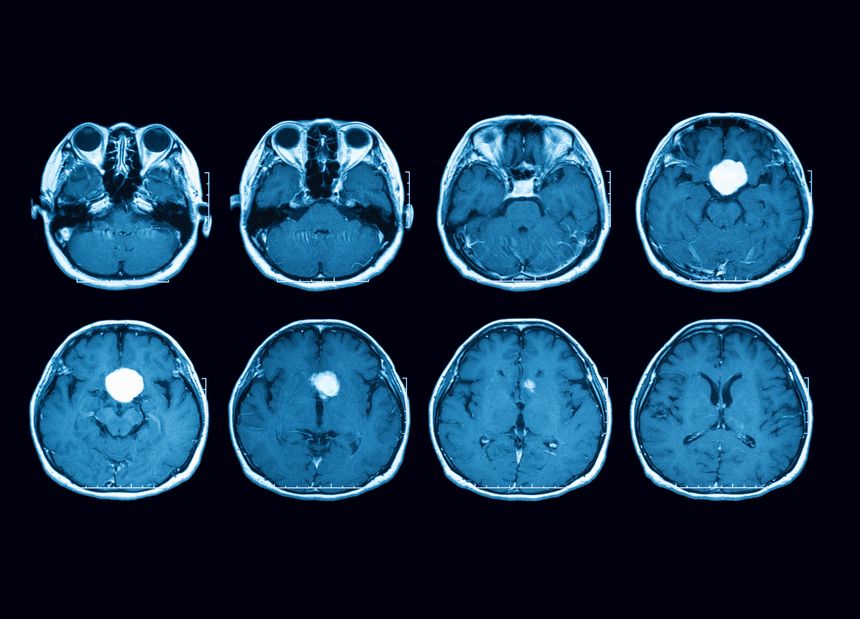

Women across the country are taking legal action against Pfizer, the manufacturer of Depo-Provera, alleging that the company failed to warn about the risks of developing meningiomas — generally non-cancerous but potentially debilitating brain tumors. These lawsuits claim that Pfizer knew or should have known about the dangers of long-term Depo-Provera use but chose not to disclose them to doctors or patients.

This is not a medical malpractice case — doctors are not the defendants. Instead, the lawsuits focus on Pfizer’s alleged negligence in failing to provide adequate warnings about the risks of meningiomas. As more affected women stepped forward to file claims, the cases were consolidated into a multidistrict litigation (MDL) in the Northern District of Florida.